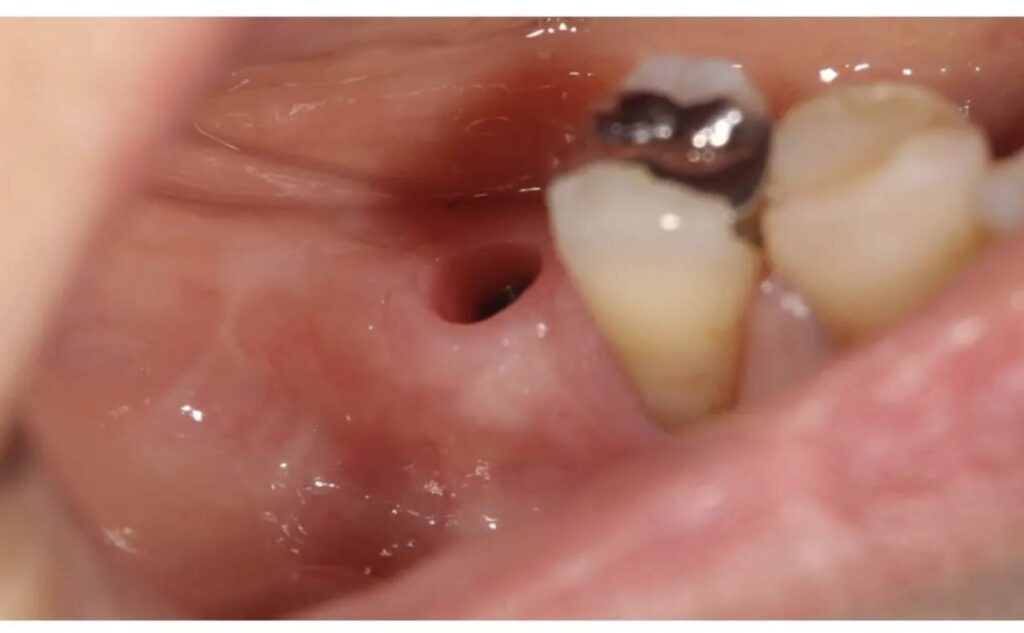

ソケットプリザベーションを行い、入れ歯からインプラントに切り替えた症例

| 年代・性別 | 60代女性 |

| 主訴 | 奥歯の違和感 |

| 診断 | 歯根破折 |

| 治療内容 | 左奥歯の1本のインプラント |

| 費用 | インプラント1本:46.2万(税込)ソケットプリザベーション:8.8万(税込) |

| 期間 | 6ヶ月 |

| リスク・副作用 | 治療後はしっかりメインテナンスを行わないと歯周病やセラミックの破折の可能性があります。 |

患者様は当院でメインテナンスをおこなっていた60代女性です。

前歯が反対咬合で、噛み合わせの力が強くかかるリスクがありましたが、ある時から右下に違和感が出始め、診断の結果、歯根破折(歯のヒビ)が見つかり抜歯を余儀なくされました。

抜歯時には、歯の周囲の骨を保存する「ソケットプリザベーション」を実施。

その後、いったん入れ歯を装着しましたが、噛みづらさが残り、よりしっかり噛める方法を希望され、インプラント治療へ移行しました。

ソケットプリザベーションを行っていたことで、骨の高さと厚みが保たれ、インプラント埋入の難易度を大幅に軽減できました。

治療後は違和感もなく、自然に噛める状態を回復。

また、今後の歯への負担を減らすために、就寝時にはマウスピースを併用し、インプラントと残存歯の両方を守るケアを継続されています。